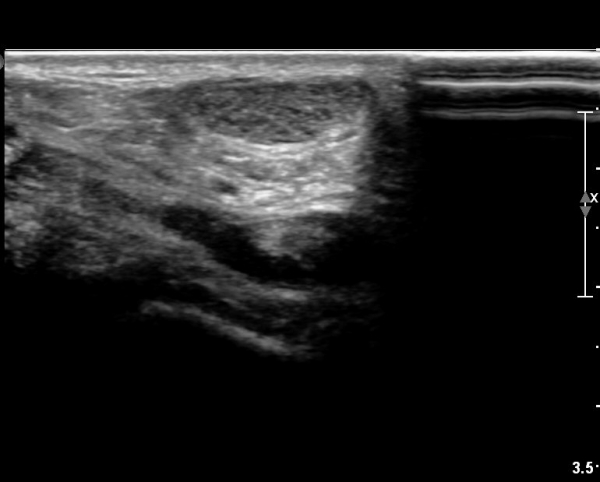

[¹ß¸ñ] simultaneosus tear of GCM and achiles tendon

abrupt leg pain developed during foot volleyball

he walk with severe limping with no weight bearing on rt. leg. on examination, there is local tendernes at GCM and achiles tendon, severe pain with ankle dorsiflexion.

ÃÊÀ½ÆÄ °Ë»ç

rec) short leg splint with crutch gait. he refused splint, then visit other hospital and took operation.